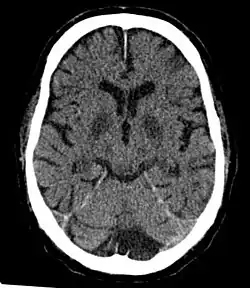

Cerebral hypoxia is a form of hypoxia (reduced supply of oxygen), specifically involving the brain; when the brain is completely deprived of oxygen, it is called cerebral anoxia. There are four categories of cerebral hypoxia; they are, in order of increasing severity: diffuse cerebral hypoxia (DCH), focal cerebral ischemia, cerebral infarction, and global cerebral ischemia. Prolonged hypoxia induces neuronal cell death via apoptosis, resulting in a hypoxic brain injury.[1][2]

Cases of total oxygen deprivation are termed "anoxia", which can be hypoxic in origin (reduced oxygen availability) or ischemic in origin (oxygen deprivation due to a disruption in blood flow). Brain injury as a result of oxygen deprivation either due to hypoxic or anoxic mechanisms is generally termed hypoxic/anoxic injury (HAI). Hypoxic ischemic encephalopathy (HIE) is a condition that occurs when the entire brain is deprived of an adequate oxygen supply, but the deprivation is not total. While HIE is associated in most cases with oxygen deprivation in the neonate due to birth asphyxia, it can occur in all age groups and is often a complication of cardiac arrest.[3][4][5]

Cerebral hypoxia is typically grouped into four categories depending on the severity and location of the brain's oxygen deprivation:[20]

- Diffuse cerebral hypoxia – A mild to moderate impairment of brain function due to low oxygen levels in the blood.

- Focal cerebral ischemia – A stroke occurring in a localized area that can either be acute or transient. This may be due to a variety of medical conditions such as an aneurysm that causes a hemorrhagic stroke, or an occlusion occurring in the affected blood vessels due to a thrombus (thrombotic stroke) or embolus (embolic stroke).[21] Focal cerebral ischemia constitutes a large majority of the clinical cases in stroke pathology with the infarct usually occurring in the middle cerebral artery (MCA).[22]

- Global cerebral ischemia – A complete stoppage of blood flow to the brain.

- Cerebral infarction – A "stroke", caused by complete oxygen deprivation due to an interference in cerebral blood flow which affects multiple areas of the brain.